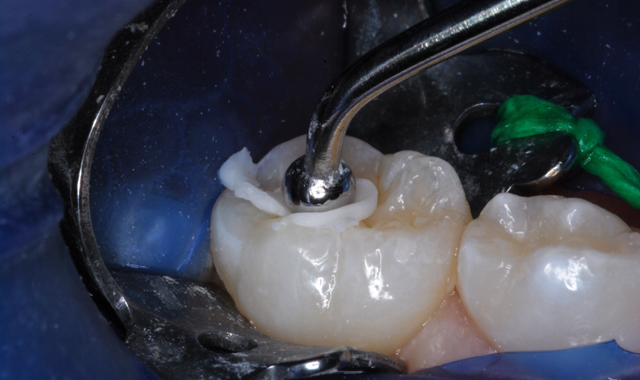

After appropriate local anesthesia, the tooth was isolated with a rubber dam, using the “slit dam” method (Fig. 2). Outline form was prepared using a high-speed diamond bur, exposing the extent of the caries lesion (Fig. 3). Carious dentin was debrided with slow-speed round burs and the cavity preparation was completed (Figs. 4 and 5).

Fig. 5 Fig. 6